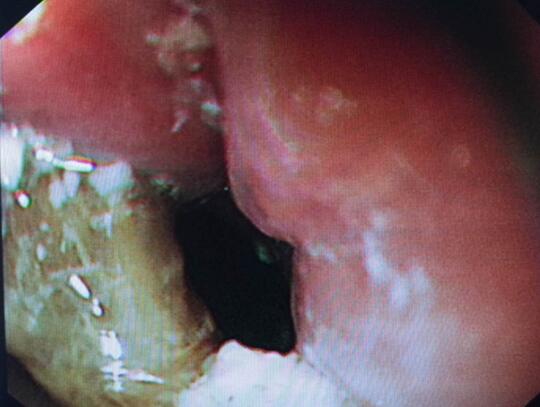

内镜中心王莹副主任考虑到患者病情复杂且高龄,不具备急诊外科手术条件,在确保患者安全情况下行内镜下异物钳取术、钛夹封闭损伤治疗。术中观察到梭形枣核嵌顿于患者食管上端,一侧食管壁可见纵形全层伤口,损伤非常严重。王主任克服困难,以她熟练的操作最终将异物顺利取出。

异物

食道损伤